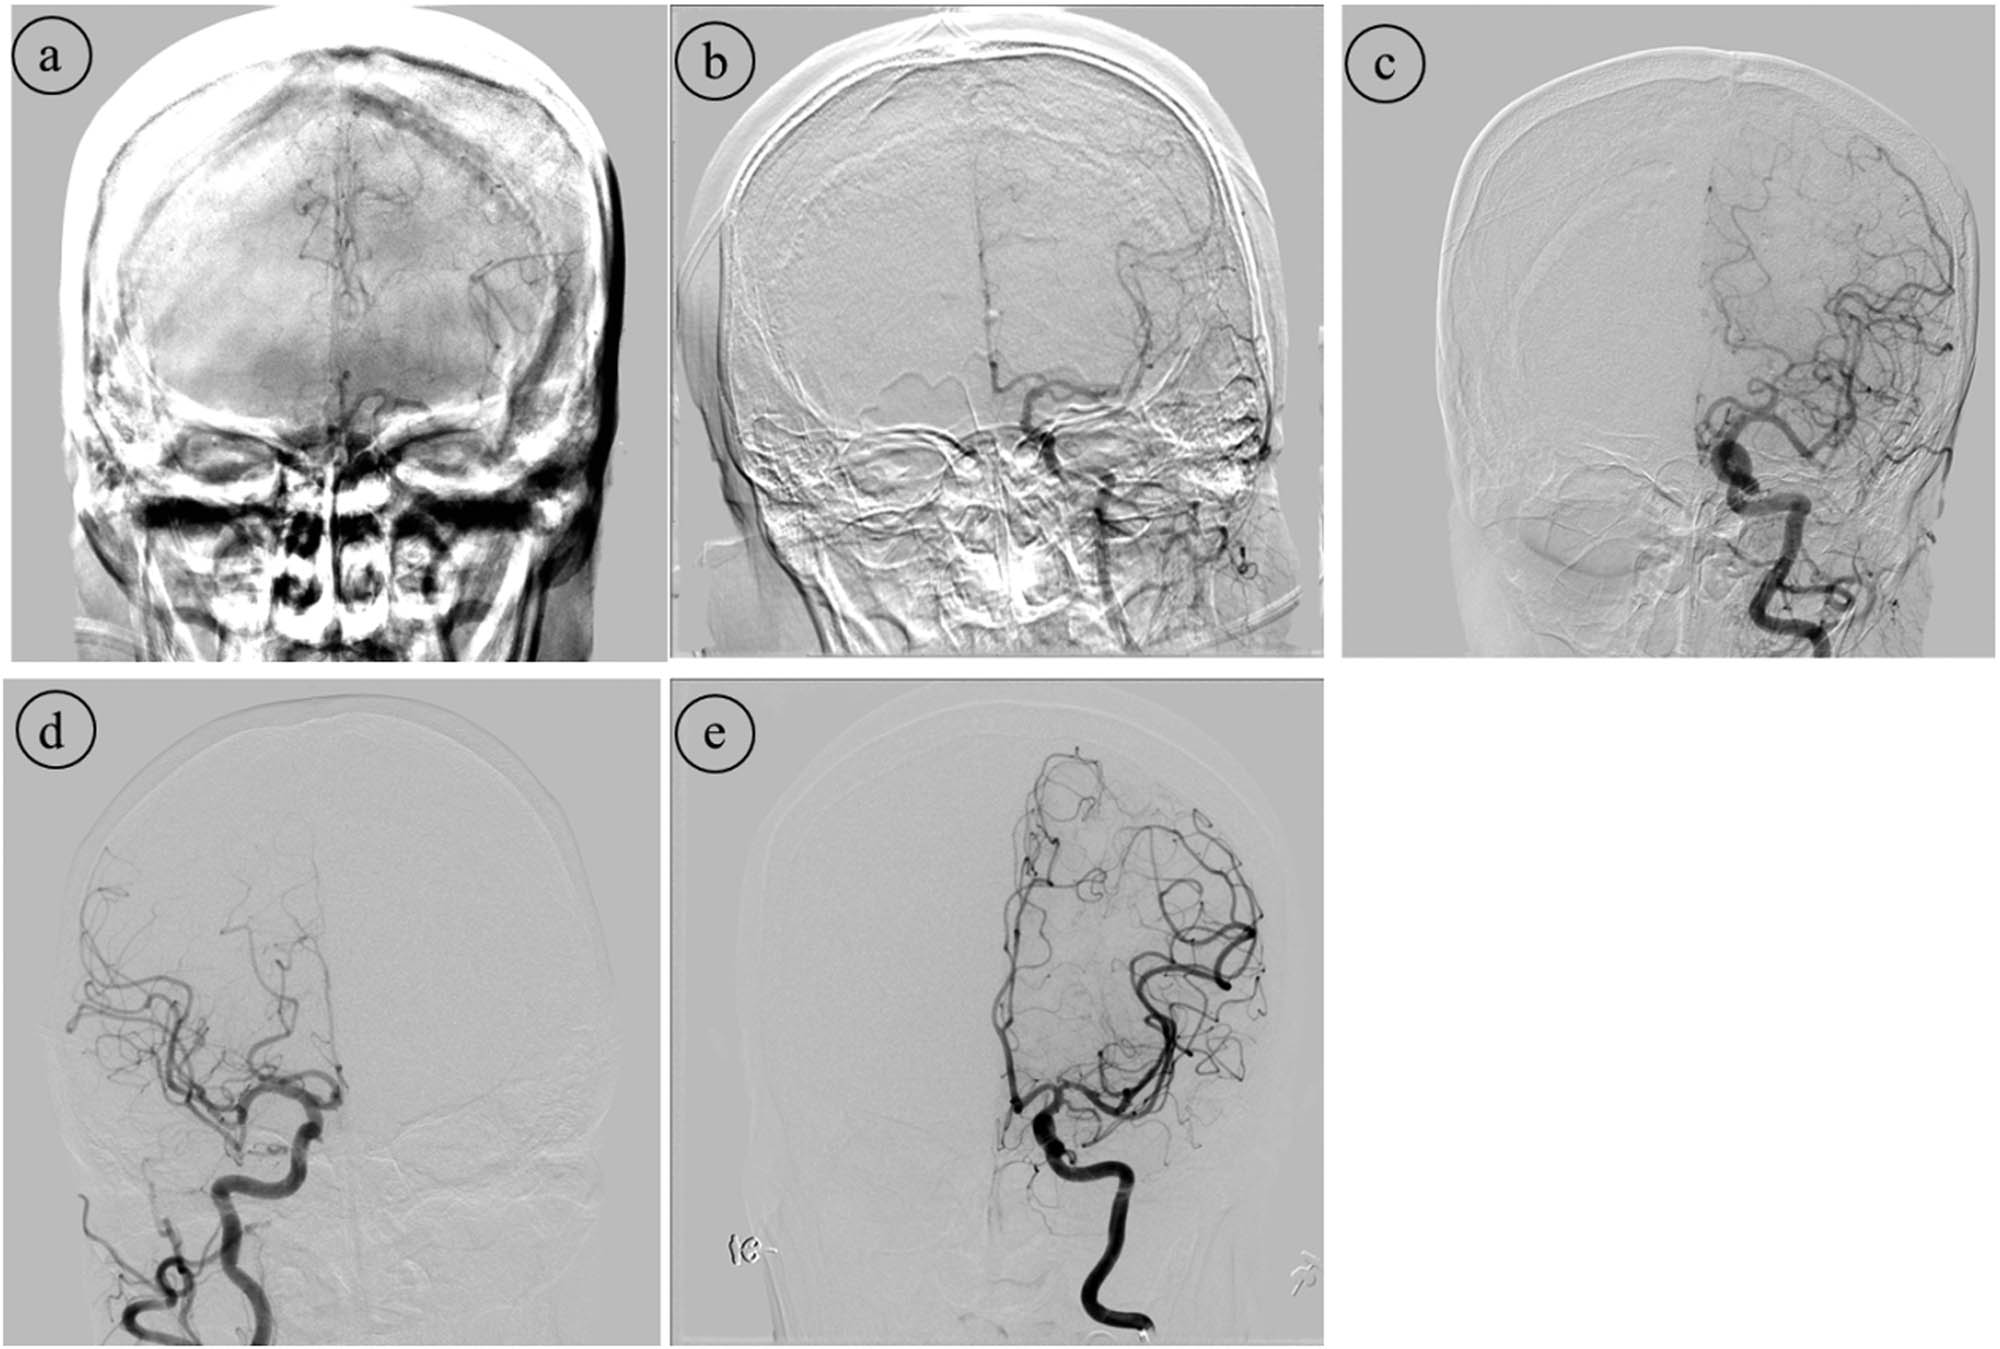

Images of ICAs and VAs in each individual were obtained for the quality assessment of anteroposterior and lateral DSA images, respectively. These images were excluded from assessment if any flow-limiting vascular stenosis/stenosis or artery steal phenomenon from arteriovenous shunts obscured relative opacification of a vessel segment or distribution. All analyses were performed in consensus by two independent neuroradiologists, each of whom has more than 5 years of clinical experience in cerebral imaging, on a system workstation (Siemens), without knowledge of the study design. Each DSA image was defined with respect to arterial, capillary and venous phases, determined by a 5-point scale on DSA images [15] (Table 1 and Figure 2) and followed by an average value of the total cumulative score.

DSA image quality score with picture illustration.